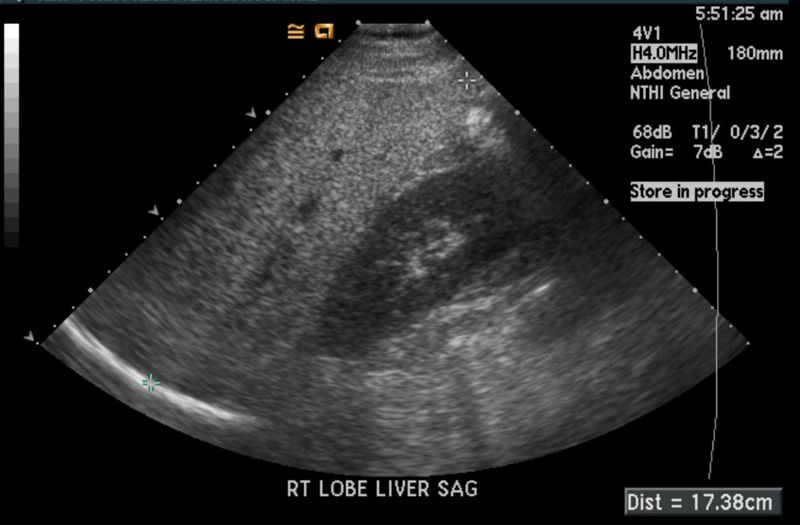

Heatomegaly

Hepatomegaly